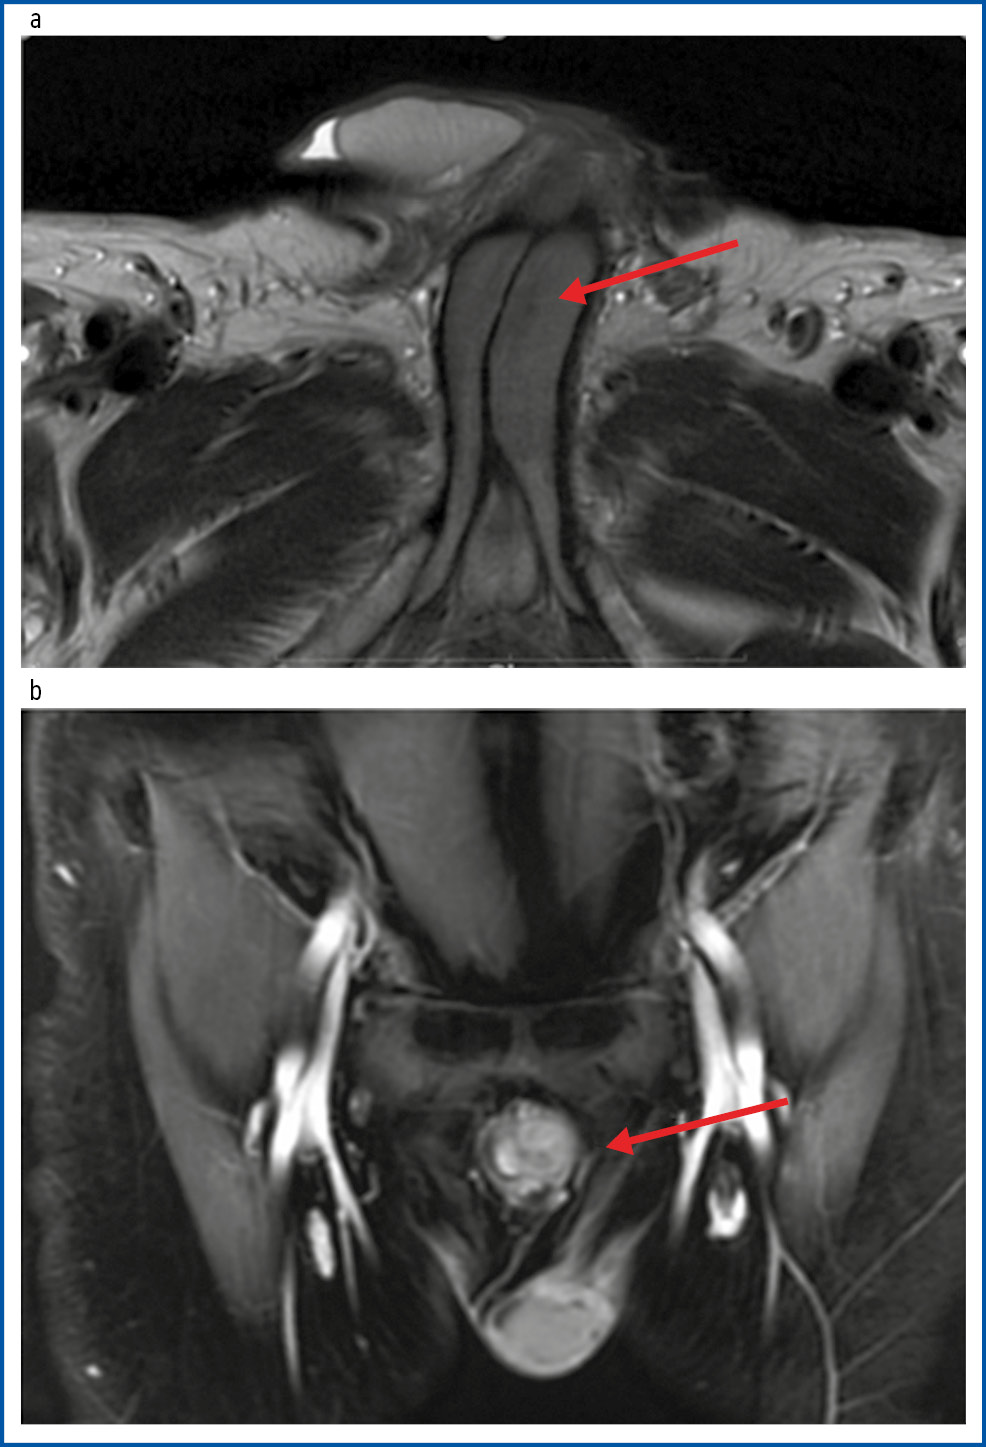

По данным МРТ малого таза с контрастированием кавернозные тела асимметричные, S>D. На Т2-взвешенных изображениях в области корня определяется неоднородность структуры с наличием гиподенсивных участков больше слева и частично справа, с нечеткими контурами, признаками ограничения диффузии, размерами 50×25 мм. При контрастном усилении отмечается неоднородное накопление контрастного препарата. Заключение: метастатическое поражение полового члена (рис. 1).

Рис. 1. Пациент Ф., 59 лет: a – Т2 МРТ-проекция, в корне полового члена в пещеристом теле слева с переходом на правые отделы определяется гиподенсивная зона; b – корональная постконтрастная МРТ-проекция, в основании полового члена слева определяется образование размером 50×25 мм, неоднородно копящее контрастный препарат.

Fig. 1. Patient F., 59 years old: a – T2 MRI view, a hypodense zone at the root of the penis in the cavernous body on the left with the transition to the right; b – coronal post-contrast MRI view; a 50×25 mm mass at the base of the penis on the left with heterogeneous contrast agent uptake.